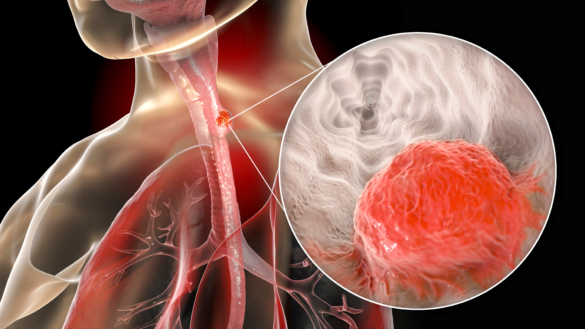

NT-rådet rekommenderar Opdivo för adjuvant behandling av avancerad esofagus- eller kardiacancer